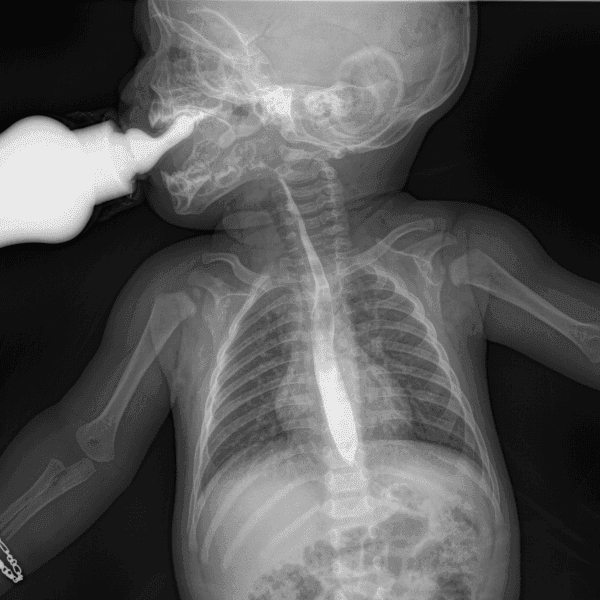

La Serie Esofagogastroduodenal (SEGD) es un estudio de radiología dinámica (fluoroscopía) que permite visualizar en tiempo real cómo el paciente traga y cómo viaja el alimento a través del esófago hacia el estómago y el duodeno.

El paciente ingiere un líquido de contraste (Bario) que es opaco a los Rayos X, permitiendo al médico radiólogo observar la anatomía y función del tracto digestivo superior en movimiento.